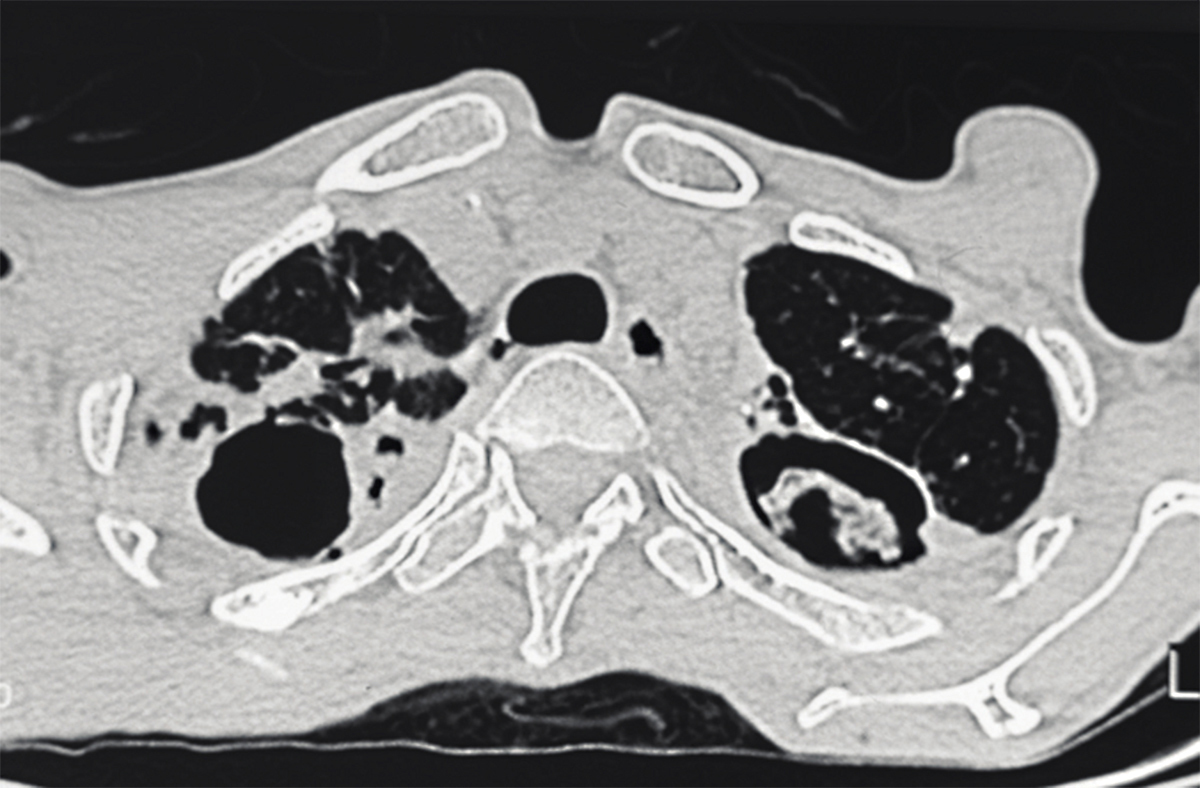

Quel est votre diagnostic ?

Il s'agit d'un aspergillome pulmonaire. L'aspergillome est un corps étranger d'origine fongique se développant dans une cavité préexistante naturelle (sinus) ou acquise (cavité secondaire à une tuberculose ou à une sarcoïdose).Il correspond à la prolifération d'Aspergillus dans une cavité pulmonaire préexistante, en l'absence de macrophages alvéolaires. C'est le cas des anciennes cavernes tuberculeuses, de la sarcoïdose, des bulles d'emphysème d'un infarctus pulmonaire ou encore d'un cancer excavé, qui peuvent être colonisés dès qu'ils sont ouverts dans les voies aériennes.L'aspergillome se manifeste par une hémoptysie, une toux, une altération de l'état général et un amaigrissement. L'aspect radiologique est le plus souvent typique : opacité dense, arrondie ou ovalaire, siégeant au sein d'une cavité. Cette masse, recouverte d'un croissant clair gazeux, peut être mobile aux changements de position, d'où l'appellation de "signe du grelot".Outre l'aspect radiologique typique, le diagnostic est confirmé par la sérologie. Son traitement curatif est chirurgical. Le traitement chirurgical idéal consiste en une résection anatomique emportant le mycétome et la cavité sous-jacente. Les candidats idéaux à une prise en charge chirurgicale sont les patients ayant un aspergillome unique et/ou des hémoptysies. Le geste de référence est la lobectomie car la segmentectomie expose à un risque accru de fuite aérienne prolongée. La pneumonectomie est associée à un risque élevée d'empyème, voire de fistule au niveau du moignon bronchique et doit être évitée. Chez les patients insuffisants respiratoires qui ne toléreraient pas une simple lobectomie, l'ouverture directe de la cavité pour réalisation d'une "truffectomie" donne de bons résultats.